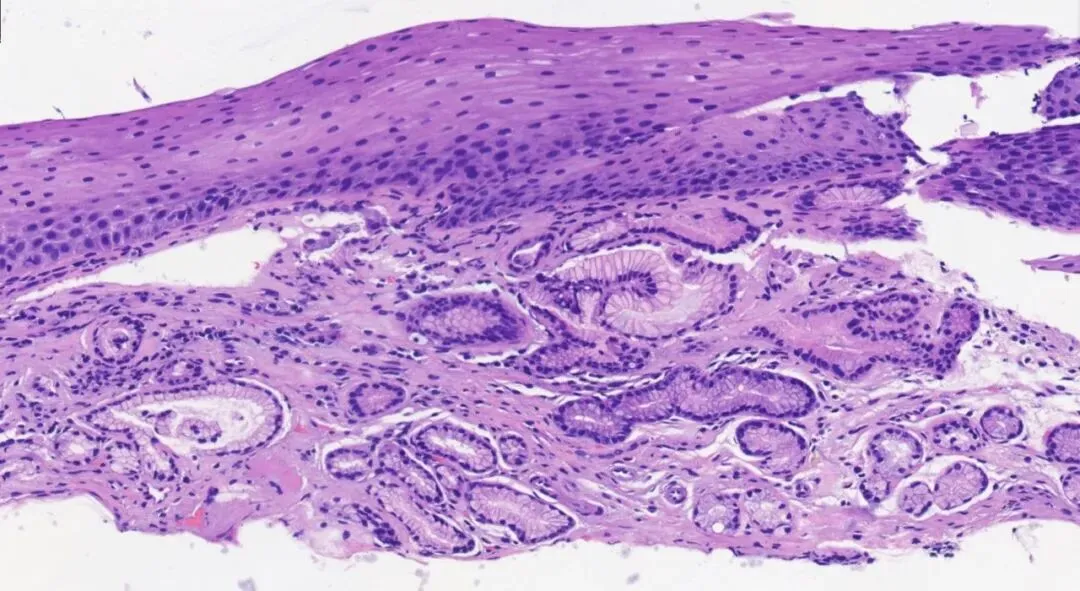

3.典型病理是鳞状上皮局灶性变薄及黏膜固有层显著增生、扩张的贲门腺。